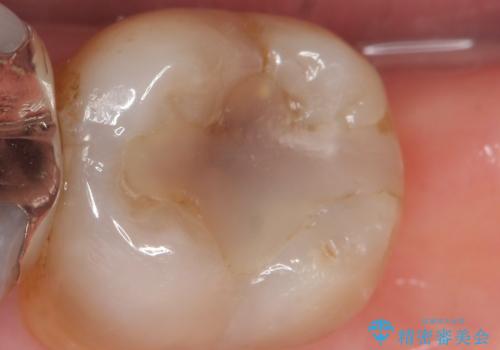

- 奥歯に以前充填した部分に時折知覚過敏があり改善を希望され来院されました。

長期的にみて劣化の早いコンポジットレジンを除去後、しっかりと噛んでいる歯なのでセラミックに比べ壊れたりかけたりすることの少ないゴールドで修復する計画を立てます。